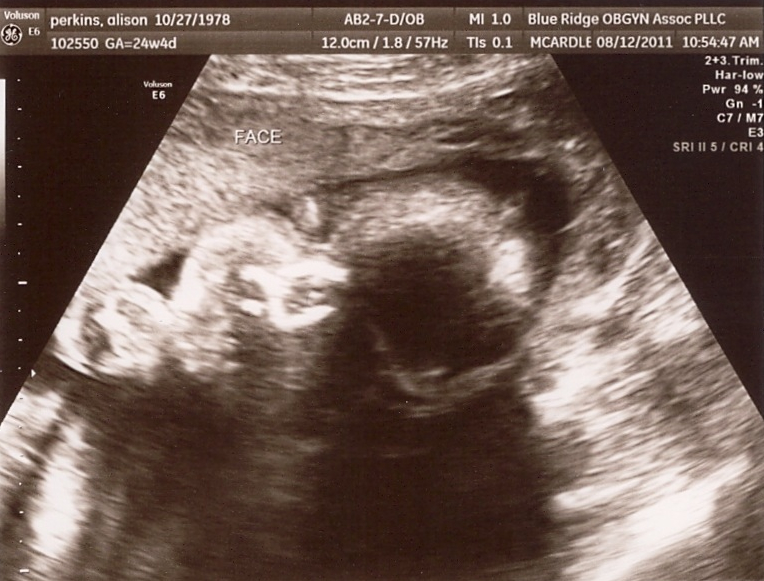

It’s a girl!